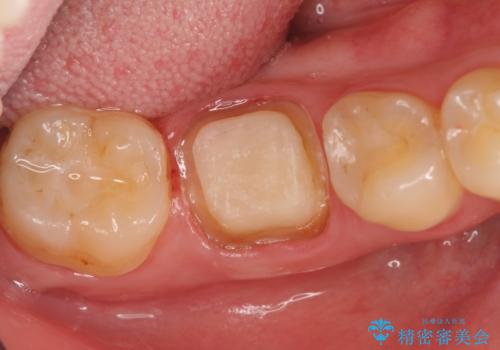

- 右下の奥歯の鈍い痛みがずっと続いているので診て欲しいといらっしゃった方の症例です。

検査の結果右下6に根尖病変を認めたため、再根管治療を行いました。

その後症状の消失を確認し、オールセラミッククラウンによる補綴を行いました。

今回用いたオールセラミッククラウンはジルコニアフレームという白い素材の上にセラミックを盛っているため、審美性が非常に高いのが特徴です。